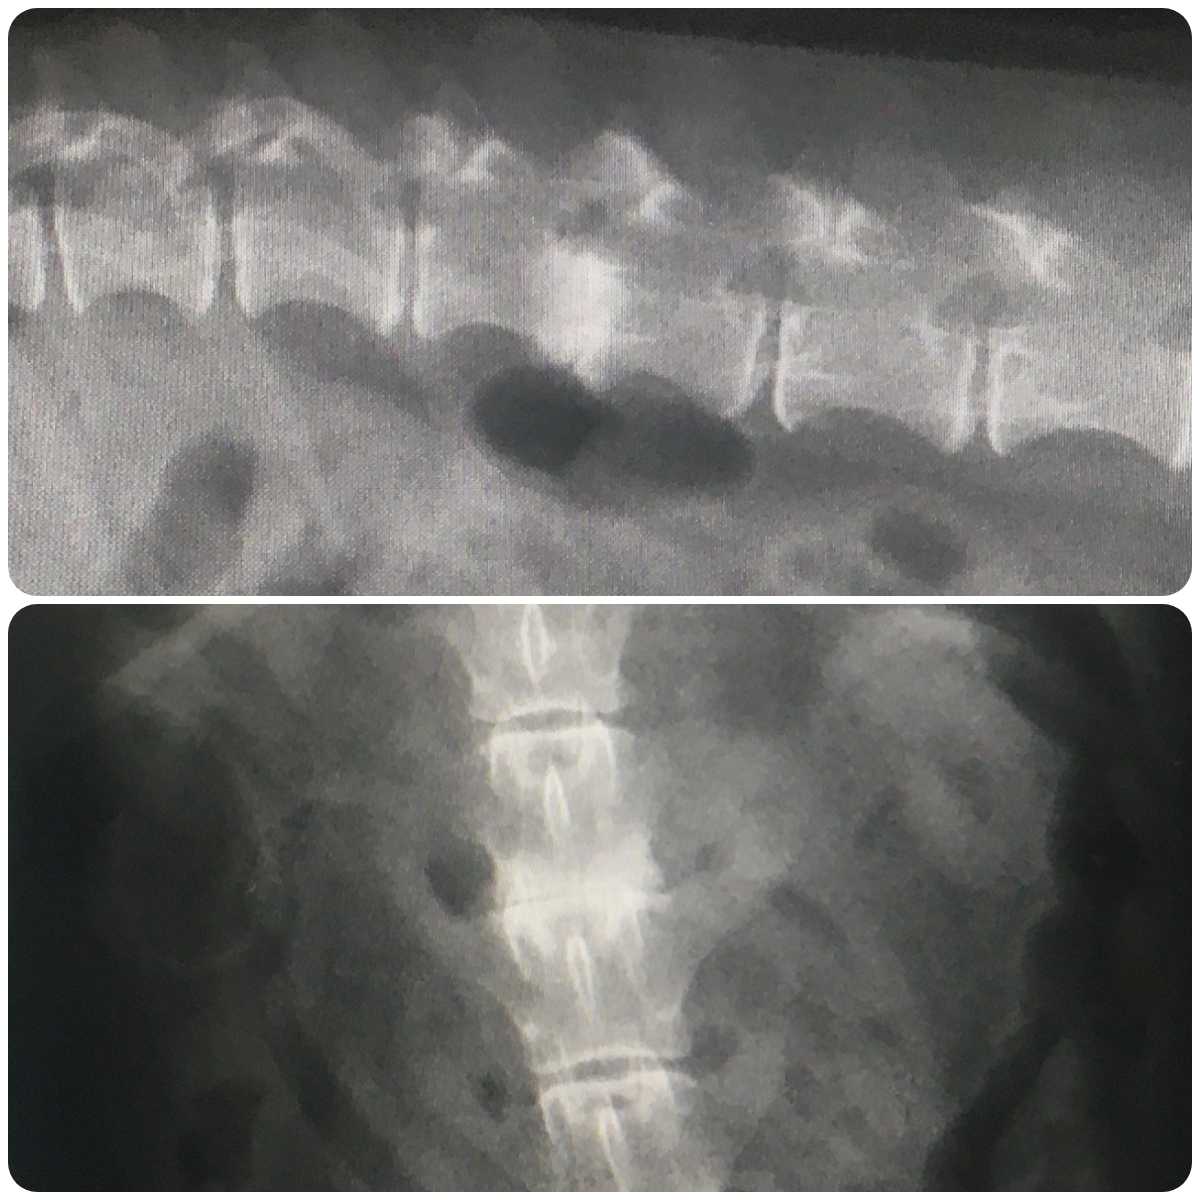

レントゲンの画像がありますので苦手な方はご遠慮ください

こちら2月に撮ったレントゲンですね

で、これは今回撮ったものです

異常は無さそうですね

2月のレントゲンもそうなんですけど、白くなってるところは何ですか?

これはヘルニアの痕ですね

症状が出ないまま治ってしまったのでしょう

軟骨部分がすり減った状態です

変形性脊椎症ではないのですか

こちらは違いますね